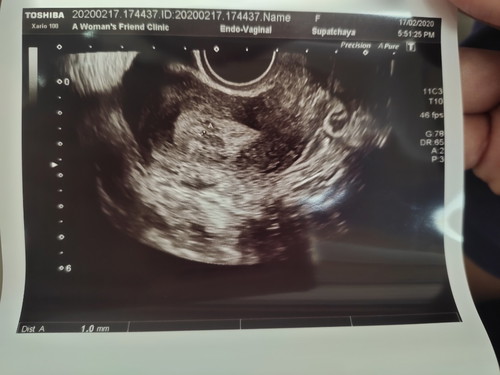

สอบถามหน่อยค่ะ เราประจำเดือนขาดประมาณ 3 วัน แล้วไปหาหมออัลตร้าซาวน์ คุณหมอบอกว่าท้องได้ประมาณ 3 weeks เจอถุงตั้งครรภ์ ขนาด 1 มิล แบบนี้ถือว่าเล็กไปไหมคะ

ประวัติเคยแท้ง กลัวท้องลมค่ะ

ปกตินะคะ รอให้สัก 8-9 วีคค่อยไปซาวด์ใหม่ดูค่ะน้องน่าจะโตกว่านี้จ้า